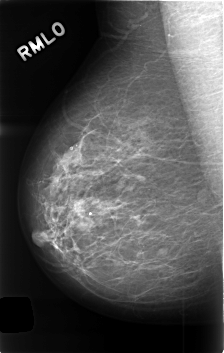

C_0408_1.RIGHT_MLO

RIGHT_CC LINES 4528 PIXELS_PER_LINE 2912 BITS_PER_PIXEL 12 RESOLUTION 50 NON_OVERLAY

RIGHT_MLO LINES 4584 PIXELS_PER_LINE 2904 BITS_PER_PIXEL 12 RESOLUTION 50 NON_OVERLAY